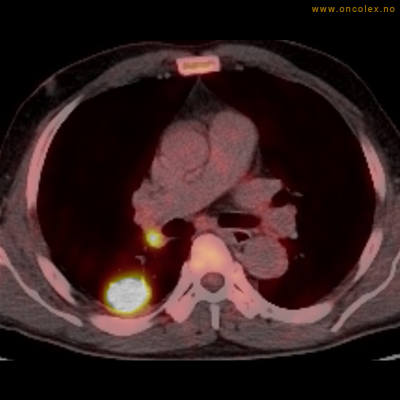

PET/CT (PET: Positron Emisjons Tomografi/ CT: Computer Tomografi) er en avansert nukleærmedisinsk bildetakingsmetode. Metoden er et godt dokumentert, veletablert og svært nyttig verktøy i bildediagnostikk ved kreft. Et PET-kamera gir tredimensjonale bilder av hele kroppen. Integrert CT gjør at informasjonen fra PET blir lokalisert anatomisk nøyaktig.

Kort beskrivelse av undersøkelsen

Gjennom en nål (plastkanyle) i en blodåre i armen vil du få et radioaktivt stoff. Det mest vanlige er radioaktivt druesukker (18F-FDG). Stråling fra det radioaktive stoffet registreres i PET-skanneren og viser hvordan dette stoffet fordeler seg i kroppen. Det normale opptaket av det radioaktive stoffet vil være endret ved sykdomsprosesser. Celler med høyt stoffskite, som for eksempel kreftceller, har økt opptak av sukker. Ved undersøkelsen kan man dermed ofte se større opptak av det radioaktive sporstoffet i kreftsvulster.  Siden CT tas samtidig, kan PET og CT bildene legges sammen og vise nøyaktig hvor i kroppen det økte opptaket er.

Eksempler på funn

Vev som tar opp mer radioaktivt stoff, synes som hvite områder som lyser opp mer i forhold til annet vev som tar opp mindre sukker.